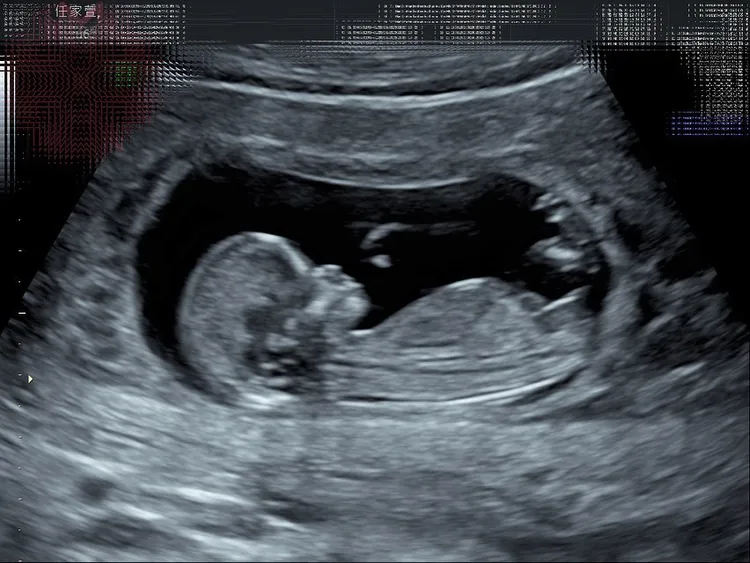

Selina坦言第一次產檢時很緊張,笑說第一次看到超音波照片「就像看到一個泡」,直到第二次產檢聽到寶寶心跳後,她立刻感動爆哭,她也坦言目前還沒有胎動,所以只有照超音波時,才會感受到寶寶和她的連結,一度激動到想網購超音波機器在家天天看腹中寶寶的動態。

Selina亮出寶寶超音波。翻攝Selina IG

Selina後來曬出胎兒超音波照,以及孕婦手冊,透露自己為寶貝取名「小腰果」,Ella稱讚「好可愛的小名喔,喜歡」,Hebe則說:「小腰果很中性,可男可女,可甜可鹹,可以帶皮也可以去皮,甚至頑皮。」她自己則期許:「腰果啊~彎彎的,似微笑的眼睛。上揚的,似笑開的嘴角!媽媽希望腰果是個快樂的小孩。」